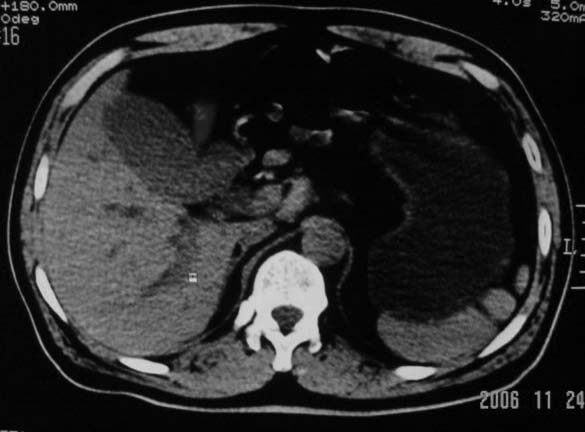

标题: CT5395:男、60岁,皮肤、巩膜黄染伴上腹部疼痛20天 [打印本页]

标题: CT5395:男、60岁,皮肤、巩膜黄染伴上腹部疼痛20天

感觉不是结石可能,与上一层面联系应该是门脉区影像,图像显示不佳,胆总管显示不清[特别是胰头以上段],目前影像只能说肝内外胆管扩张,胰管扩张,胆囊扩大。提示胆总管远端梗阻。可考虑肿瘤或结石所致

胆总管内结节状高密度灶,边缘隐约可见低密度环绕,首先考虑结石伴肝内胆管扩张; 2、胆囊增大,胆囊炎

肝内外胆管及胰管均示有扩张,胆囊增大.提示胆总管远端梗阻,可考虑肿瘤或结石或肿瘤伴结石,建议强化扫描

1.肝内外胆管扩张,楼主箭头所示处多系结石.

2.图象太黑,窗位太高,窗宽太窄,解剖结构显示欠佳 .